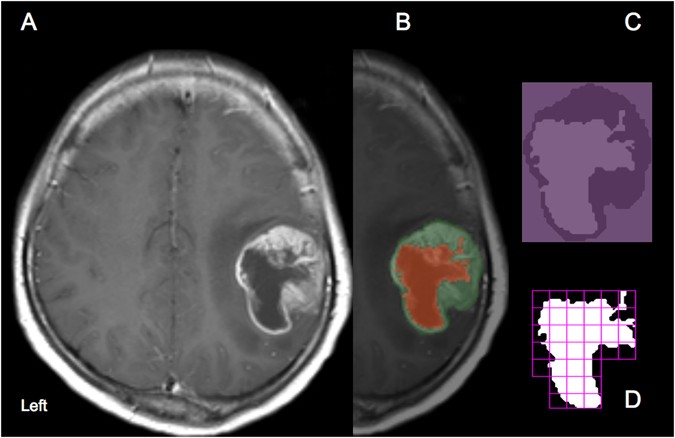

We report two patients who had a single, large lesion on magnetic resonance imaging (mri) of the brain. Often an mri scan can reveal the tumor type, but in many cases, a biopsy is required. Giant cerebral tuberculoma is an uncommon but serious form of tuberculosis. In general, diagnosing a brain tumor usually begins with magnetic resonance imaging (mri). Proper treatment, planning, and accurate diagnostics should be implemented to improve the life expectancy of the patients. Certain malignancies are also characteristic. malignant brain tumor is also termed as 'brain cancer, due to its metastasis nature and often associated with life threatening health issues. A brain tumor occurs when abnormal cells form within the brain.

There are two main types of tumors: Both patients underwent neurosurgery for the excision of the mass lesion as neuroimaging findings were suggestive of a brain tumor. Certain malignancies are also characteristic. But although the symptoms of most brain tumors are the same, not all tumors are malignant. Proper treatment, planning, and accurate diagnostics should be implemented to improve the life expectancy of the patients. Magnetic resonance imaging (mri) and computed tomography (ct) scans are used most often to look for brain diseases. Giant cerebral tuberculoma is an uncommon but serious form of tuberculosis. mri scans can help medical professionals detect cancer. These can be further classified as primary tumors, which start within the brain, and secondary tumors, which most commonly have spread from tumors located outside the brain, known as brain metastasis tumors. brain tumors are classified as: In particular, they rarely spread to other parts of the body and typically produce symptoms due to localized growth within the brain. These scans will almost always show a brain tumor, if one is present. brain tumors are classified based on where the tumor is located, the type of tissue involved, whether the tumor is benign or malignant, and other factors.